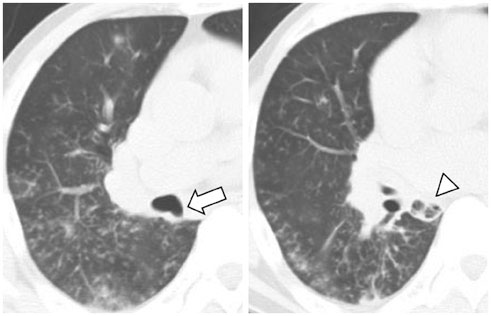

We identified two main types of ACB: blind-end (51.7%) and lobule (48.3%). The blind-end ACB was further classified into three subtypes: blunt (70%), pointy (23.3%) and saccular (6.7%). The lobule ACB was also further classified into three subtypes: complete (46.4%), incomplete (28.6%) and rudimentary (25%). Division location to the upper half bronchus intermedius (79.3%) and medial direction (60.3%) were the most common in all patients. The difference in division direction was statistically significant between the blind-end and lobule types (p = 0.019). Peribronchial soft tissue was found in five cases. One calcification case was identified in the lobule type. During follow-up, ACB had disappeared in two cases of the blind-end type and in one case of the rudimentary subtype.

The proposed classification of ACB based on imaging, and the follow-up CT, helped us to understand the various imaging features of ACB.